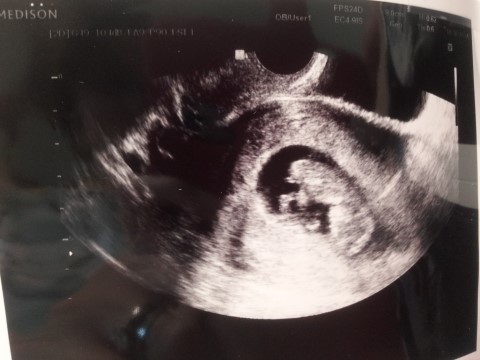

**[임신 21~24주] 홍이랑 나~^^- 임당검사 & 정밀초음파검사

{ 북가좌아줌마 BaBy BaBy } + ++ +++ &nb...